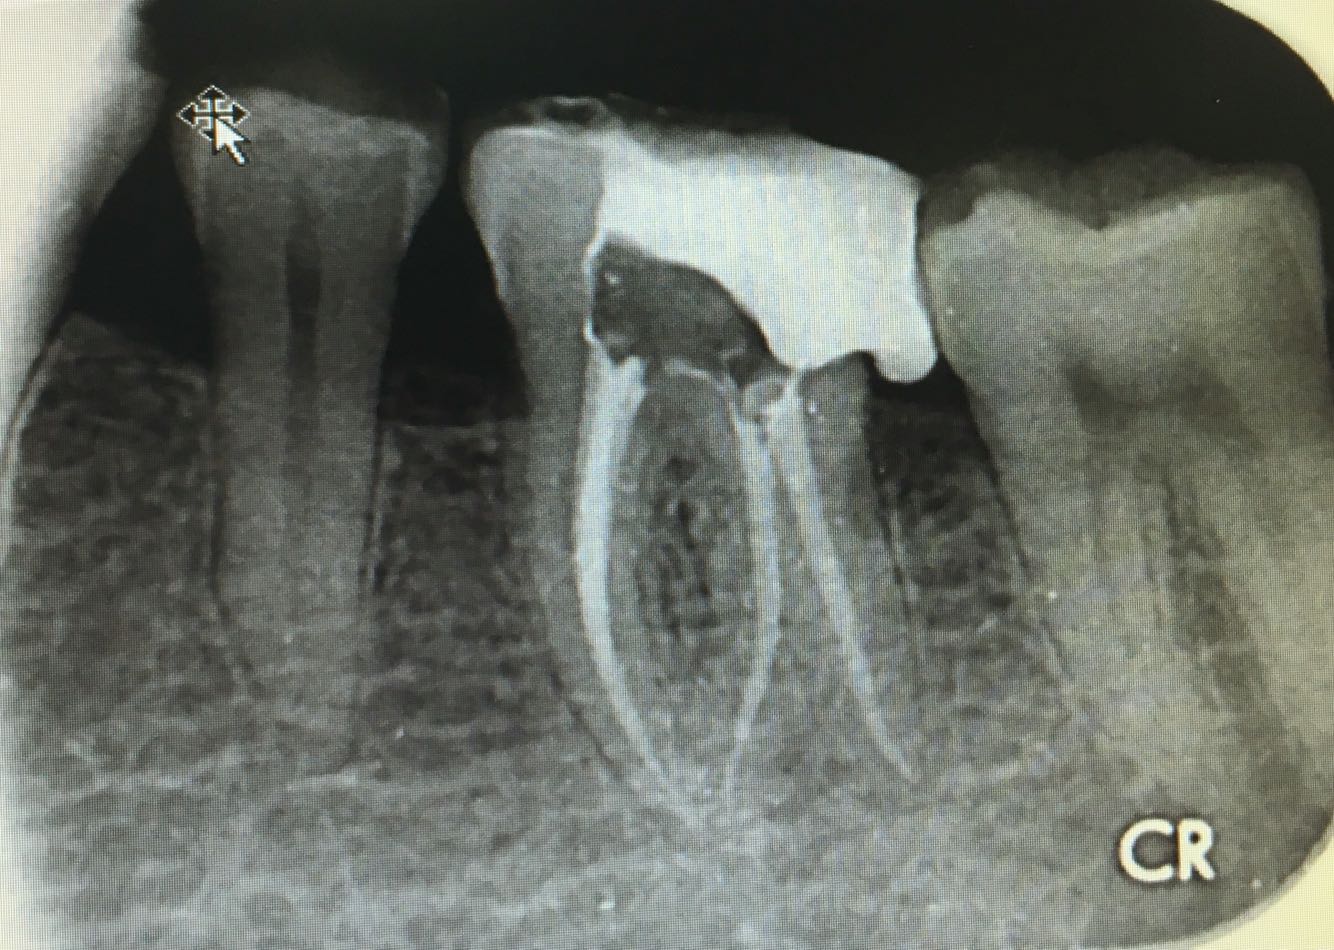

检查:左下 6 合面白色暂封物,冷测无反应,探(-) ,叩(-) ,不松,龈正常,根尖相应粘膜处无红肿及压痛。 X 片示:左下6冠部高密度充填影像与髓腔穿通,根尖周正常,髓腔无钙化,远舌根管弯向近中

处置:左下6 去 ZOE,开髓孔无探痛,揭顶,拔髓,探及 M2D2 四根管,10#锉疏通各根管,测 WL: MB=19mm, ML=19mm, DB=18mm, DL=18.5mm, EDTA下,常规预备至F2,3%过氧化氢和0.9%生理盐水冲洗+超声荡洗根管交替进行。隔湿,干燥根管,氧化糊剂牙胶尖冷侧压充填,ZON暂封。嘱勿用患牙咬物。 2周后复诊,冷(一),叩痛(一),不松,牙龈无红肿,去除暂封物,牙体组织预备,流动树脂垫底填除倒凹,电子影像取模,送CAD/CAM制作高嵌体。 3日后复诊,嵌体配戴,调合,抛光,树脂粘接剂永久粘接。 患者对修复效果满意,交待患者使用注意事项。